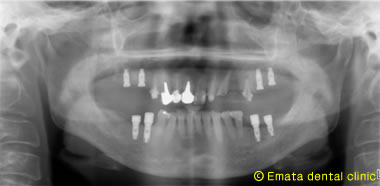

昨日は上顎(上あご)左右2本ずつ4本インプラントを埋入しました。

患者さんはできるだけ早くインプラントの手術を終わらせたいとの(期間と回数)希望でした。

手術時間は約1時間ですが、静脈内鎮静法を行ったので患者さんはオペ終了までほとんど何も覚えてらっしゃらないのでとても楽でした。3週間前に下顎(下あご)を左右同時に4本埋入したので1ヶ月で上下左右8本のインプラントの手術を終えました。

しかし歯周病の初期治療には2ヶ月かかりました。インプラント治療を成功させるためには歯周病の問題を解決しないといけませんね。

術前のレントゲン |